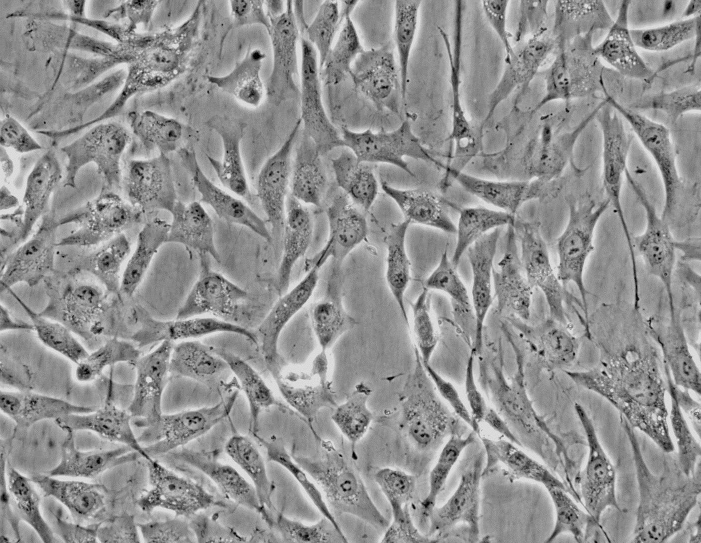

上皮细胞样

SK-OV-3

中文名称:人卵巢癌细胞

形态:上皮细胞样

背景资料:SK-OV-3由G.Trempe和L.J.Old在1973年从卵巢肿瘤病人的腹水分离得到。 此细胞对肿瘤坏死因子和几种细胞毒性药物包括白喉毒素、顺铂和阿霉素均耐受。 在裸鼠中致瘤,且形成与卵巢原位癌一致的中度分化的腺癌。